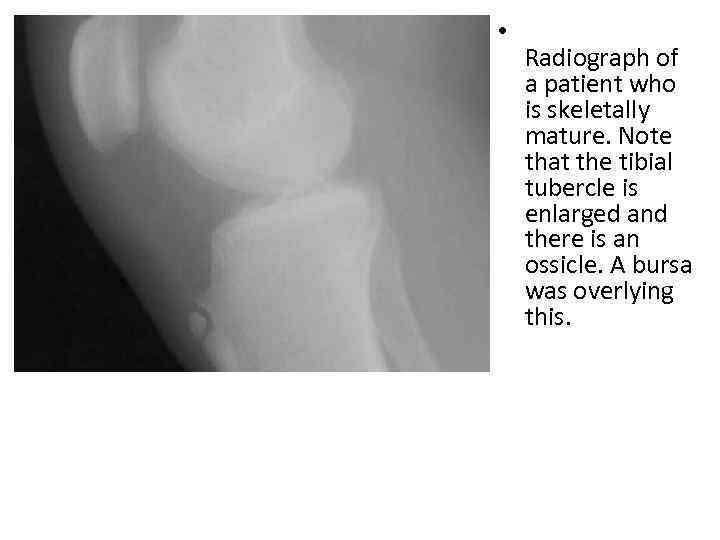

• Radiograph of a patient who is skeletally mature. Note that the tibial tubercle is enlarged and there is an ossicle. A bursa was overlying this.

• The acute phase of OSD may reveal a prominent and elevated tibial tubercle with anterior soft-tissue swelling. • In severe cases, radiographs may reveal radiodense fragments or ossicles separated from the tibial tuberosity. (An ossicle is seen in the image below. ) • Radiograph of a patient who is skeletally mature. Note that the tibial tubercle is enlarged and there is an ossicle. A bursa was overlying this. • View Media Gallery • Occasionally, the radiographs may reveal irregularity, fragmentation (seen below), or increased density of the ossification of the tibial tubercle. This pattern may be a normal variant in asymptomatic children.